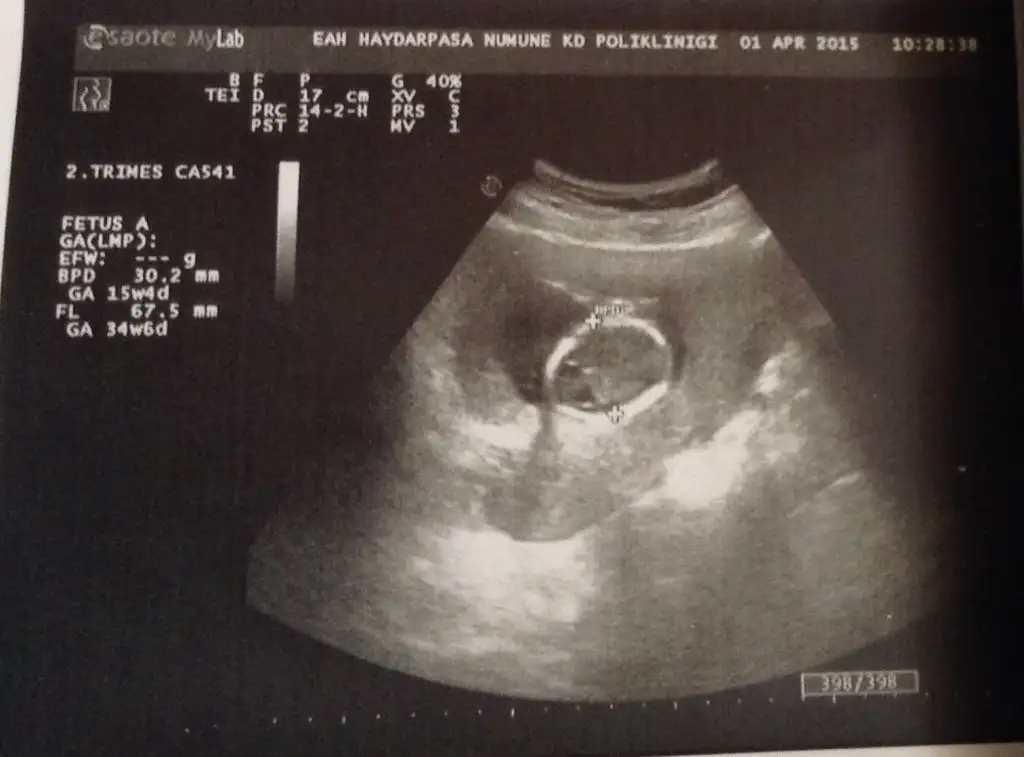

Dünki resimleri birinde başını diğerinde kolunu ölçtü dr. Burdan cinsiyet tahmini yapabilir misiniz? yada içinizden geçen :)

20150402_123451.webp

20150402_123333.webp

:KK3:Kızlar bana da yardımcı olurmusunuz? Var mı tahmini olan. Benim minigimde burda:KK54: